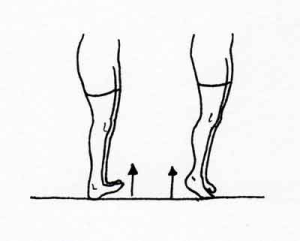

- بلند کردن پاشنه – پنجه

مطابق تصویر شماره ۶ صاف بایستید و به آرامی و تا حد ممکن انگشتان خود را به سمت بالا بکشید. انگشتان را پایین آورده و به آرامی پاشنه را بالا بکشید و فشار را بر گوشت زیر انگشتان وارد نمایید. این حرکت را چندین نوبت در روز و هر نوبت، ۱۰ بار تکرار نمایید.

تصویر شماره ۶، تمرین شماره ۱: بلند کردن پاشنه-پنجه